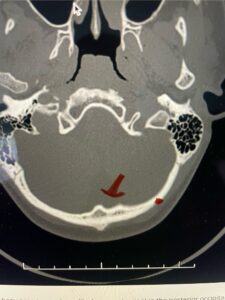

Cervical x-rays revealed a significantly increased atlanto-axial interval (Fig. 5) On review of her imaging studies it was noted that the right C2 isthmus was very thinned by the vertebral foramen (Figs 6a, b, and c) which would make an attempt at placing a C2 pars screw dangerous. A decision was made to perform an occipital-cervical fusion because only possible unilateral fixation and an extensive C1 laminectomy to be performed eliminating a fixation point if a more traditional C1-C2 was performed. Even if C1 lateral mass screws were able to be placed one could only perform a unilateral screw construct fixation to C2. We performed an occipital cervical fusion down to C4 to get enough inferior fixation and C1 laminectomy. The decompression went well. We placed a left unilateral pars screw and bilateral C3 and C4 lateral mass screws. We placed three 12 mm screws in the midline keel (Fig. 7). Postoperatively the patient had all around improvement in her symptoms and did not qualify for rehab. Her post op films at 6 weeks (Fig. 8)

Fig. 6c: Axial cervical CT scan demonstrating a very thin right C2 isthmus (red arrow) compared to left side.